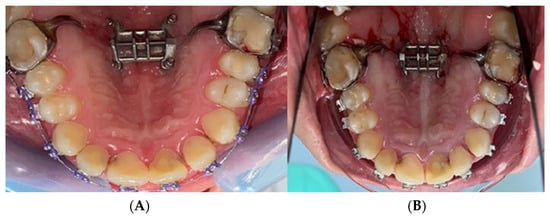

2.2. Palatal Expander Placement

2.3. Assessment of the Study Group